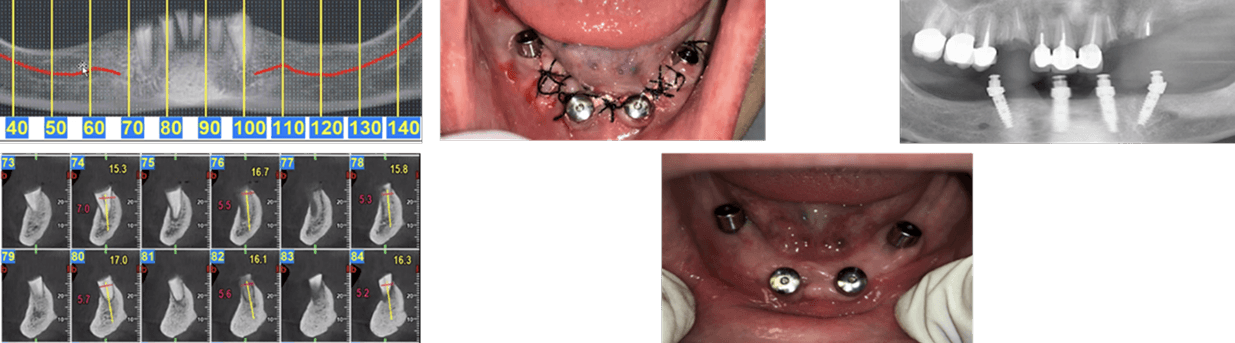

Inflammatory environment Regeneration (Dr. Eli Raviv, Associate Professor, McGill University). A patient presented with severe inflammatory environment, showing a probing depth of 6 mm and advanced bone loss. The implant was initially considered non-salvageable and scheduled for extraction, especially as an adjacent implant had previously been removed due to the same condition. The case represented a critical-stage peri-implant infection, typically associated with poor prognosis and progressive bone destruction.

Instead of proceeding with implant removal, Dr. Eli Raviv implemented a regenerative, non-surgical treatment protocol using the Magdent MED healing abutment. The first MED device was placed for 30 consecutive days, delivering localized Pulsed Electromagnetic Field (PEMF) stimulation directly to the peri-implant site. After completion of the first cycle, a second MED was installed for an additional 30 days to extend the stimulation period and maximize regenerative outcomes. Throughout the treatment, no additional surgical intervention was performed.

• Within weeks, the site showed marked improvement in soft tissue tone and reduction of inflammation.

• At 1 year, clinical measurements revealed a reduction of pocket depth from 6 mm to 2 mm—representing a 200% improvement in clinical attachment level and return to healthy peri-implant conditions.

• At 15 months follow-up, the implant remained fully functional and stable, with no bleeding on probing, no radiographic bone loss, and complete resolution of the previous inflammatory lesion.

• This case demonstrates the potential of MED-based PEMF therapy to reverse severe inflammatory environment in cases once deemed unsalvageable, providing a non-invasive, regenerative alternative that restores implant stability, bone integrity, and long-term peri-implant health.